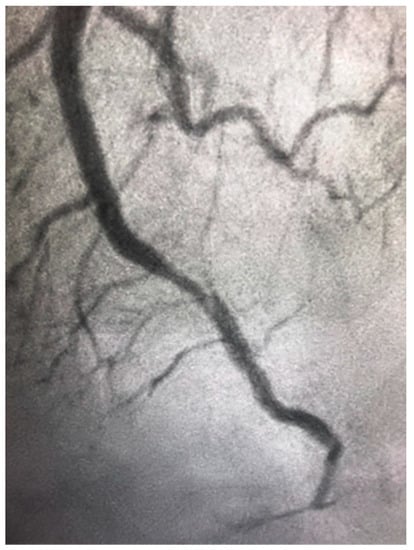

The differential diagnosis of MINOCA should include Takotsubo cardiomyopathy. This is a syndrome of transient ventricular apical ballooning (Figure 3). It has a female predilection with women accounting for over 90% of the cases [62]. The pathophysiology is catecholamine induced and not atherosclerotic in nature, although there is an increasing awareness of overlap syndromes of Takotsubo with CAD, with ACS playing a potentially causal role [63]. The pathophysiology of this syndrome is complex. The catecholamine surge causes a predominantly microvascular dysfunction—due to multiple factors including microvascular spasm and ensuring myocardial stunning, direct catecholamine cardio-toxicity, and an increase in the myocardial energy demand [64].

Figure 3.

Left ventricular angiogram in a 56-year-old patient with Takotsubo Cardiomyopathy.